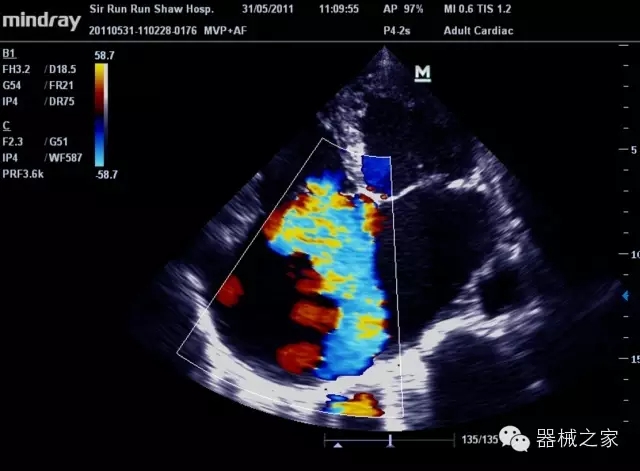

臨床圖片賞析

產(chǎn)品特點(diǎn)